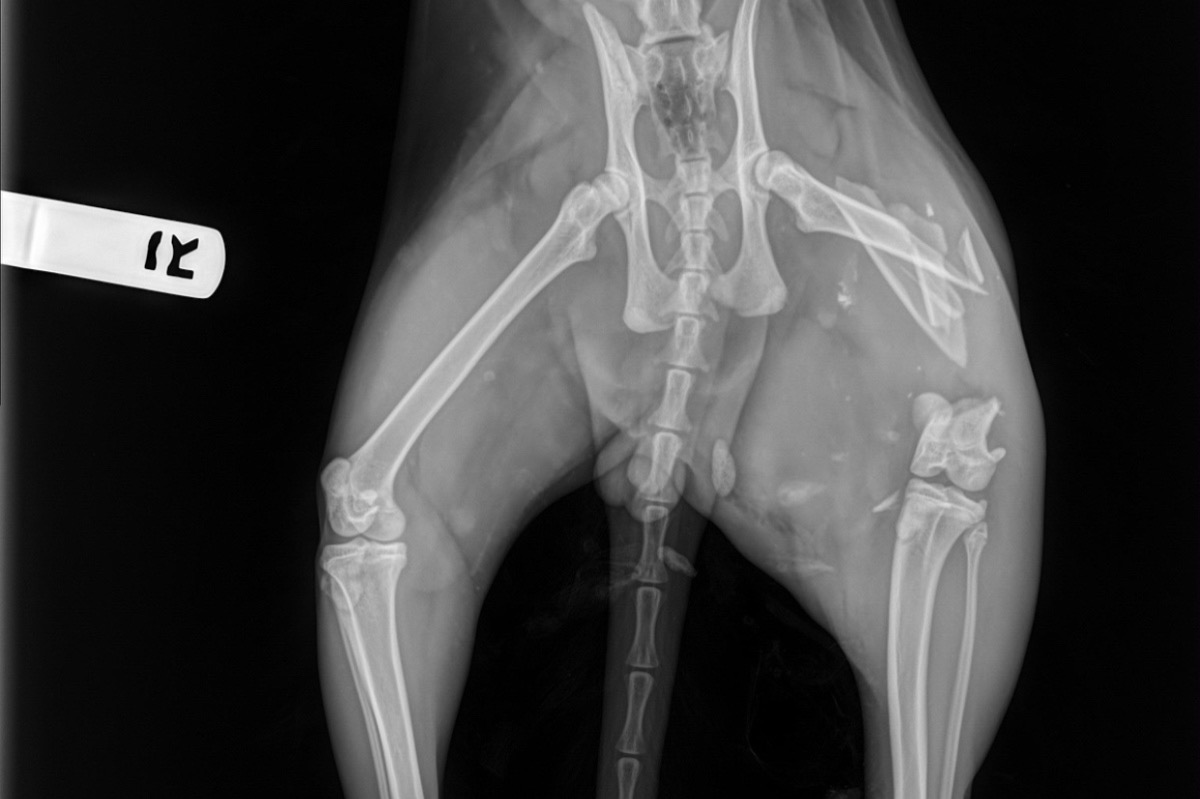

He had been hit by a car. Kitty was almost lifeless. his breath was shallow and deteriorating, his eyes were rolling while his left hind leg was dangling. I ran to my husband (who was giving our 19 month old twins a bath) we stealthy packed up the car and drove to the closest veterinarian hospital. The doctor sedated him to get x-rays and to relive the pain. After the X-rays his vitals were taken. His temperature had dropped so severely the vet urgently wrapped him up in heating blankets and hooked him up to fluids. Doc fed him some vitamins and glucose through the IV to keep him going. The radiography showed no visible signs of internal bleeding but the blood test told a different story. Although he wasn't bleeding internally, the diagnostic test showed that his liver and kidneys were struggling to preform from the impact of the car, not catastrophically enough for emergency surgery but enough to cause concern. He hasn't been able to urinate since and we've been taking him into the vet to relieve his bladder while we await surgery.

As for the X-ray results, we were informed that his femur had shattered into 7 pieces and that the trauma was too great to save his leg. Plating the leg would consist of multiple surgeries with subsequent physical therapy for months and even then there was no guarantee that he would actually be able to use the leg again. After consulting with one another, the orthopedic surgeons agreed that amputation would be the best bet and the most cost effective. Still a whopping 6,000 for the amputation. This doesn't include the overnight care, medication, check ups, or any other variable that may come into affect. This is on top of the 2,000 we have already spent just to diagnose the problem. Kitty is due to get his surgery Tuesday March 31st, one week after this tragic accident.